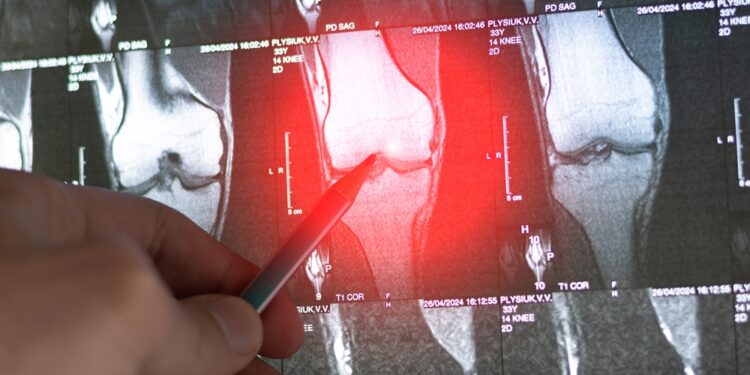

- Vaizdiniai tyrimai – rentgeno nuotraukos, kompiuterinė tomografija ar magnetinis rezonansas, leidžiantys pastebėti skaidulinio audinio sankaupas ar kaulų deformacijas